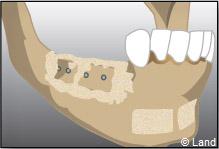

Les différentes étapes :

Prélèvement du greffon au niveau du site donneur

Apposition et stabilisation du greffon.

Recouvrement du greffon avec de l’os synthétique et une membrane

Après 6 mois de cicatrisation, il est possible de poser les implants qui recevront dans un deuxième temps les couronnes.

Apposition et stabilisation du greffon.

Recouvrement du greffon avec de l’os synthétique et une membrane